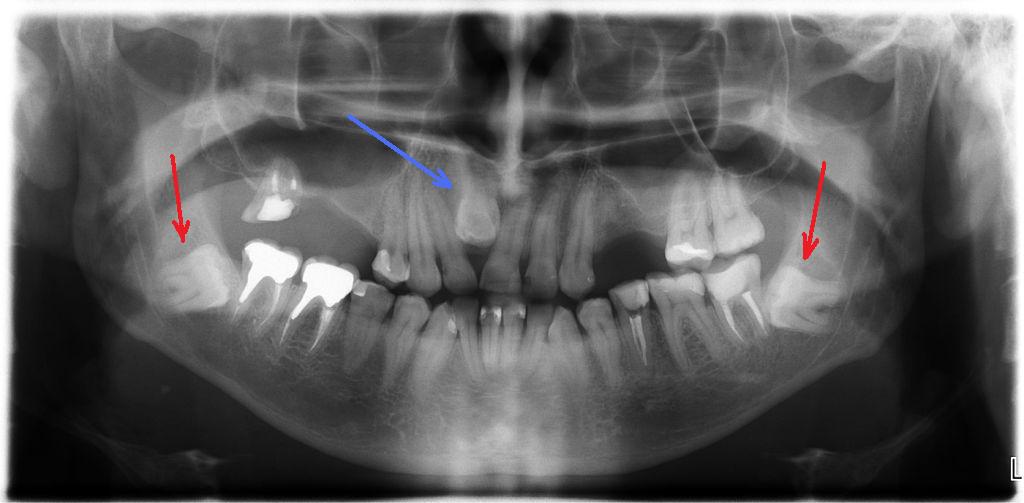

Дентальная галерея: ретинированный зуб клык и его лечение

Раздел: Компас решений